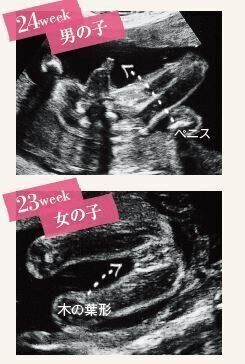

3. 【医師監修】産科医がビジュアルで解説します!「超音波写真(エコー写真)の見方」ガイド